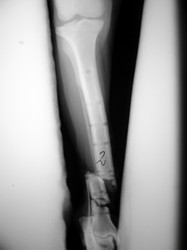

Fijación Externa

PRÁCTICAS CURSO DE FIJACIÓN EXTERNA PERFECCIONAMIENTO.

Híbrido.